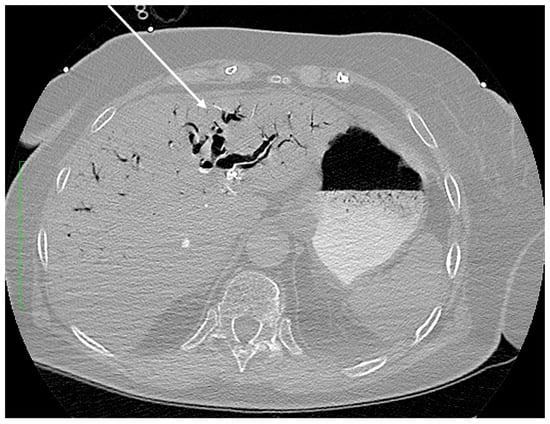

Figure 1. Axial plane of the abdominopelvic CT scan after intravenous contrast administration (lung window) at the level of the liver. Extensive intrahepatic gas is visible within the bile ducts (arrow).

The pathway of CO2 gas transmission also occurs by the biliary tract; the gas then enters the vessels of the circulatory system through the injured endothelium. The pathomechanism and incidence of this complication are multifactorial. The type of endoscopes used and the working pressure of the gas used, the type of intervention, the presence of biliary-venous fistulas, the state of the mucosal barrier, previous endoscopic interventions or the presence of implanted foreign materials are all significant [3]. All these factors result in a breach of the endothelial and tissue barrier with the transmission of gas into the vascular system—the portal vein runoff or the hepatic venous system. Figure 1 shows bile ducts filled with gas. The transmission of CO2 into the superior vena cava system occurred via damage to the endothelial tissue barrier between the bile ducts and the hepatic veins.